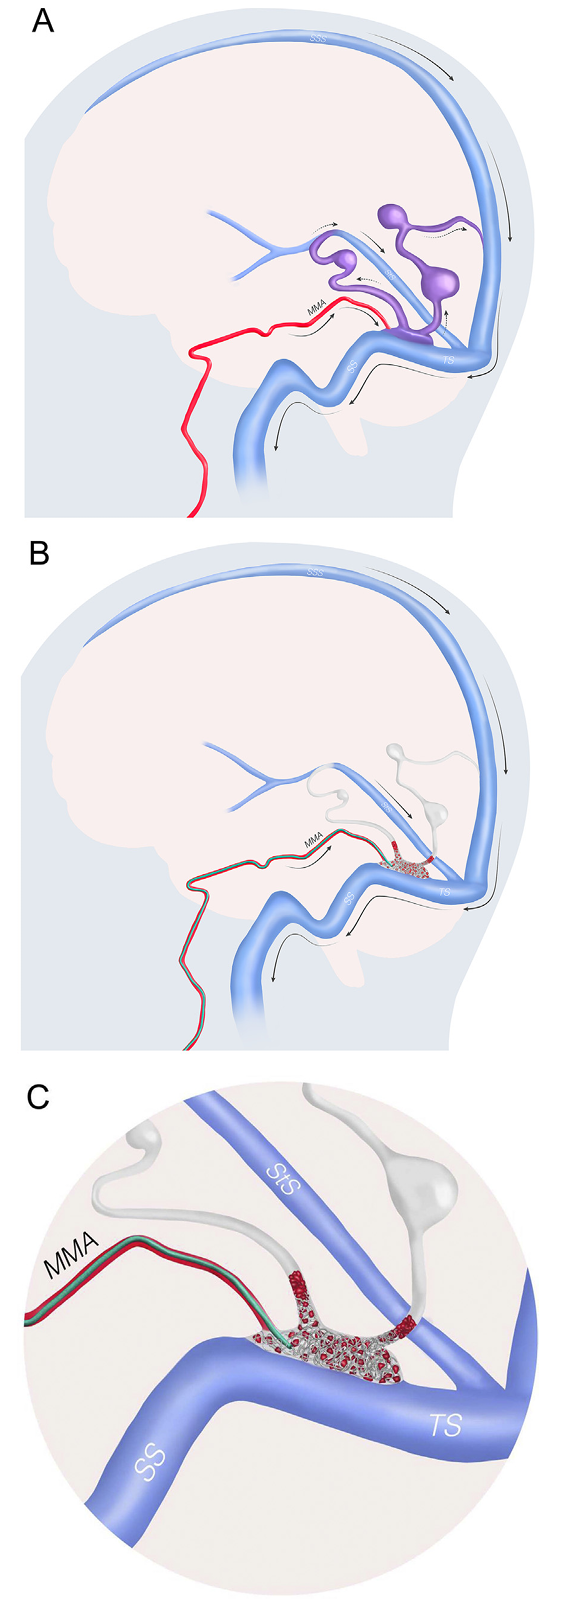

Fig. 3. Illustration demonstrating the transfistulous approach (TFA). A. Lateral view of a dural arteriovenous fistula supplied by the middle meningeal artery draining into both dilated cortical and deep veins with focal ectasias. The middle meningeal artery feeder connects to the so-called foot of the vein, consisting of the primary proximal venous drainage located in the tentorium near the transverse sinus. The direction of blood flow is shown by arrows. B. The TFA is performed by transarterial catheterization of the middle meningeal artery, navigating a low-profile microcatheter through the fistulous point into the proximal venous outlet, followed by deployment of coils. C. Enlarged view showing positioning of the microcatheter and coil deployment in the proximal venous outlet, causing thrombosis and occlusion of the fistula. When a two-directional proximal venous drainage is present, as shown here, both venous exits should preferentially be packed with coils. In patients with suitable anatomy, this approach may allow for complete fistula occlusion in a single session. The technique is particularly useful when enlarged arterial feeders are present, such as in patients with longstanding high-grade dural arteriovenous fistulas. MMA: Middle meningeal artery; SS: Sigmoid sinus; SSS: Superior sagittal sinus; StS: Straight sinus; TS: Transverse sinus.